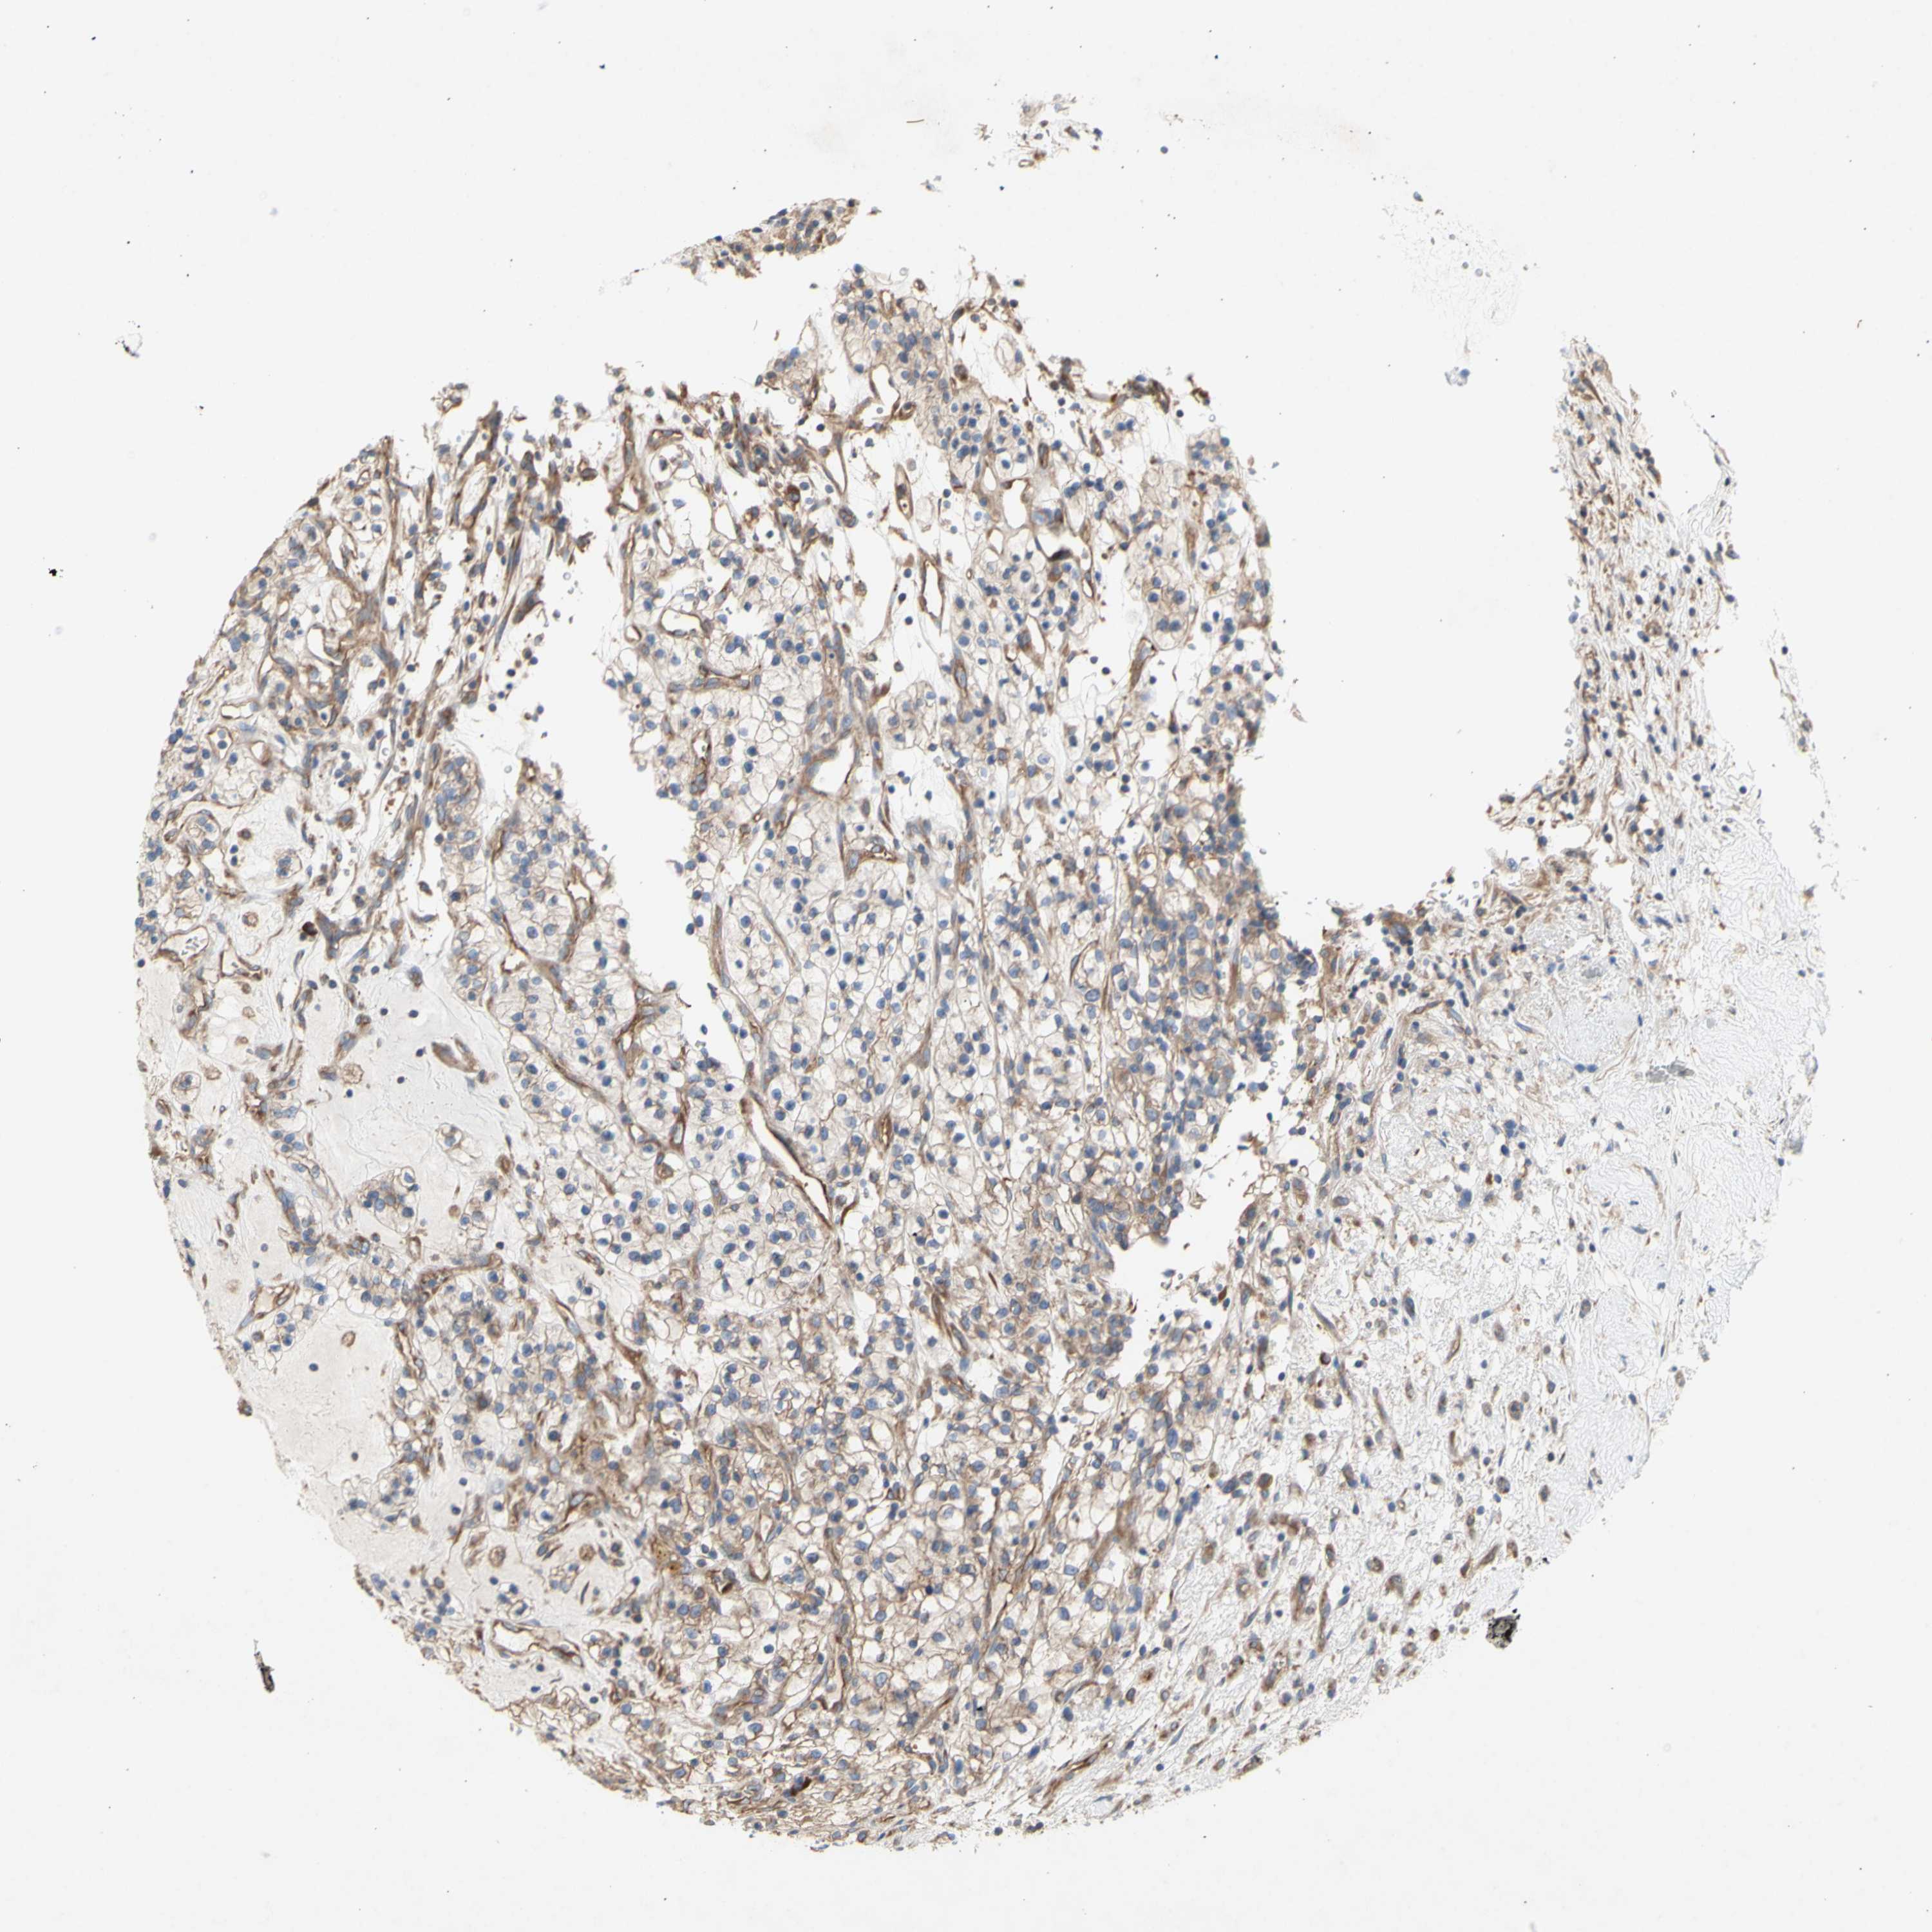

KIDNEY RENAL CLEAR CELL CARCINOMA (VALIDATION) - Interactive survival scatter ploti

The Survival Scatter plot shows the clinical status (i.e. dead or alive) for all individuals in the patient cohort, based on the same data that underlies the corresponding Kaplan-Meier plots. Patients that are alive at last time for follow-up are shown in blue and patients who have died during the study are shown in red.

The x-axis shows the expression levels (FPKM) of the investigated gene in the tumor tissue at the time of diagnosis. The y-axis shows the follow-up time after diagnosis (years). Both axes are complimented with kernel density curves demonstrating the data density over the axes. The top density plot shows the expression levels (FPKM) distribution among dead (red) and alive patients (blue). The right density plot shows the data density of the survived years of dead patients with high and low expression levels respectively, stratified using the cutoff indicated by the vertical dashed line through the Survival Scatter plot. This cutoff is automatically defined based on the FPKM cutoff that minimizes the p-score. The cutoff can be changed by dragging the vertical line or by entering a cutoff value in the square labeled "Current cut-off".

Under the Survival Scatter plot the p-score landscape (black curve; left axis) is shown together with dead median separation (red curve; right axis). Dead median separation is the difference in median mRNA expression between patients who have died with high and low expression, respectively. It is calculated as follows: median FPKM expression of dead patients with high expression - median FPKM expression of dead patients with low expression. This is intended to aid the user in visually exploring custom cutoffs and the associated p-scores and dead median separation.

Individual patient data is displayed and can be filtered by clicking on one or more of the category buttons on the top of the page. Categories describing expression level and patient information include: high, low, alive, dead, female, male and tumor stages. The scale of the x-axis can be toggled between linear and log-scale by clicking on the "x log" button. Mouse-over function shows TCGA ID, patient information and mRNA expression (FPKM) for each patient.

& Survival analysisi

Kaplan-Meier plots summarize results from analysis of correlation between mRNA expression level and patient survival. Patients were divided based on level of expression into one of the two groups "low" (under cut off) or "high" (over cut off). X-axis shows time for survival (years) and y-axis shows the probability of survival, where 1.0 corresponds to 100 percent.

KLC1 is not prognostic in Kidney Renal Clear Cell Carcinoma (validation)

: 46.41

Average pTPM 43.9